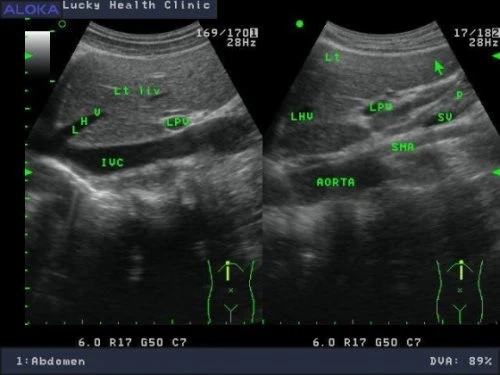

正常肝臟![]() Rt liv :右葉肝臟 IVC :下腔靜脈 hepatic V :肝靜脈 ![]() Lt liv :左葉肝臟 , LHV :左側肝靜脈 , LPV :左側肝門靜脈 , IVC :下腔靜脈 , SMA :上腸繫膜動脈 , SV :脾靜脈 , P :胰臟 , AORTA:主動脈 肝癌 ![]() 肝硬化合併早期肝癌1.4公分 ![]() 轉移性肝癌 ![]() 肝癌局部復發 1.6 公分 ![]()